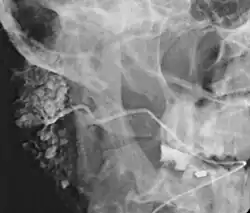

![]() Sialogram in a patient suspected of Sjögren's syndrome | |

Sialography (also termed radiosialography) is the radiographic examination of the salivary glands. It usually involves the injection of a small amount of contrast medium into the salivary duct of a single gland, followed by routine X-ray projections.[1]

The resulting image is called a sialogram.

This study is interpreted by evaluating the morphology of the salivary ducts for obstructions and chronic inflammation. Sialodochitis is a term describing dilation of the ducts caused by repeated inflammatory or infective processes. There is also irregular salivary duct stricture (narrowing) of the duct, which creates an appearance known as "sausage link" pattern on a sialogram. Suggestions of abscesses and autoimmune diseases such as Sjögren syndrome can also be elicited. Sialadenitis is inflammation of the salivary glands, which may cause acinar atrophy and create an appearance known as "pruning of the tree" on a sialogram, where there are less branches visible from the duct system. A space occupying lesion that occurs within or adjacent to a salivary gland can displace the normal anatomy of the gland. This may create an appearance known as "ball in hand" on an sialogram, where the ducts are curved around the mass of the lesion.[6]